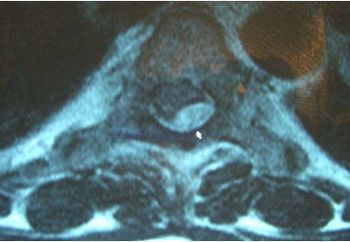

Spinal problems include epidural abscess, paravertebral muscle atrophy, Chiari I malformation, osteomyelitis/discitis, diastematomyelia, spinal compression, spinal tuberculosis.

An obese woman in her thirties with a history of fibromyalgia syndrome, depression, polycystic ovarian syndrome, and diabetes mellitus presents to her local emergency department with 1 week of gradually worsening midline back pain.